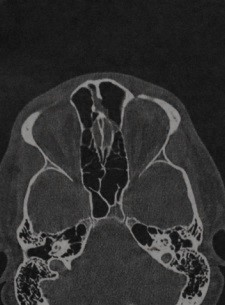

МРТ внутренних слуховых проходов в аксиальной проекции:

(а) Т1 до введения контраста.

(б) Т1 после введения гадолиния (обратите внимание на усиление сигнала от сигмовидного синуса и слизистой околоносовых пазух).

(в) Т2 (ликвор и глазные яблоки выглядят яркими),

а, мозжечок; b, сосцевидный отросток; с, четвертый желудочек; d, сонная артерия; е, сигмовидный синус;

f, улитка; д, сонная артерия; h, височная доля; i, мостомозжечковый угол (обратите внимание на слуховой и нижний вестибулярный нервы, которые входят во внутренний слуховой проход).